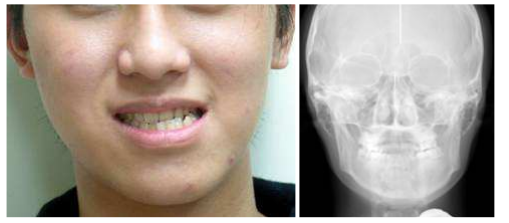

18.下圖為成年男性的正面臉部相片及X光片,下列敘述何者錯誤? (A)此病例之可能診斷為下顎骨骼性不對稱 (B)此張放射線片可能為posteroanterior(PA)cephalometric radiograph (C)當臨床上懷疑有臉部不對稱時,lateral cephalometric radiograph為最好的診斷根據 (D)齒列矯正配合正顎手術可以是本病例治療計畫的選項之一